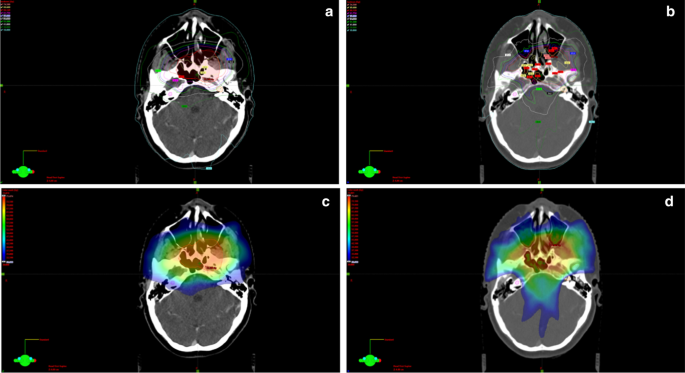

Two or three coplanar or non-coplanar arcs were used according to the complexity and location of the PTV. The field size was defined by the jaw openings allowing for a jaw tracking in the optimizer. For the counterclockwise arcs (CCW) the jaw was closed to 2 cm from the isocenter on the × 1 axis and on the × 2 axis for the clockwise arcs (CW), allowing for better cochlear sparing. The collimator angle for each plan was individually chosen from minimum ± 5 degrees based on the patient anatomy. A rapid arc model (RAM) was used for the optimization. Objectives and priorities for the OARs and/or target volumes were changed when needed so that an optimal plan could be achieved. The main differences in the re-planning were the cochlea optimization-structures used in the optimizer and the optimization way. We expanded the cochlea with 3 mm margin to ensure sparing of the original structure. In the optimizer, both expanded and original structures were used. Furthermore, we used a Rapid arc model in the optimizer and “manual” normal tissue objectives for all plans (this was the case only in some of the original plans). Also, different collimator angles and jaw openings were implemented. More precise, for all cases of the re-optimized plans following procedures were applied: the jaws were closed for each beam so that the cochlea would remain outside the treatment field when possible, or as much as close to the cochlea if very close to the PTV. On the CW arcs the right cochlea was outside the treatment field, while the left one on the CCW arcs. Jaw tracking on the optimizer was allowed. Regarding the collimator angles the differences were minimal: 5-degree and 355-degree angles were often used for the re-optimized plans, while for the reference plans 3 degrees and 357 were more common. In the few cases of overlapping between the cochlea and the PTV we aimed to spare the cochlea on the opposite side, similar to the original plan. The resulting plan was re-optimized until a clinical acceptable plan was achieved. An example for the comparison between original and re-optimized plan is shown in Fig. 1.